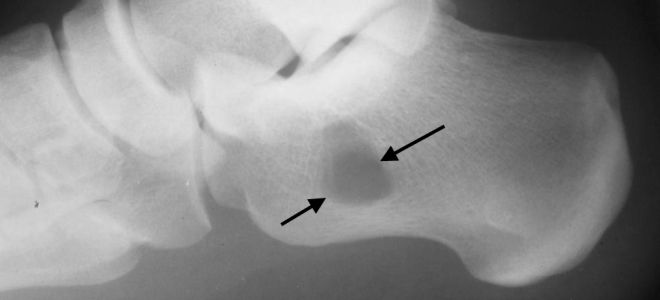

При подозрении на болезнь Шинца рентгенография становится одним из первых методов обследования, назначаемых пациенту. Исследование пяточного бугра на начальной стадии заболевания показывает уплотнение. Это приводит к расширению пространства между пяточной костью и пяточным бугром. На рентгеновских снимках специалисты могут заметить неравномерную структуру ядра окостенения, а также явные участки разрыхления кости с корковым веществом.

На более поздних стадиях заболевания наблюдаются отдельные фрагменты бугра. Также обращают внимание на признаки формирования нового губчатого вещества. В случаях, когда диагноз остается неясным, проводят сравнительное исследование обеих пяточных костей. Для уточнения диагноза пациента могут направить на компьютерную томографию (КТ) или магнитно-резонансную томографию (МРТ).